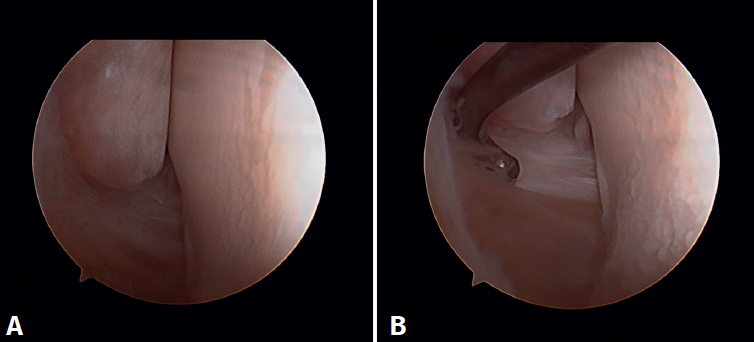

Arthroscopic anatomy of the medial complex

Arthroscopy allows us to see the deep fibers of the deltoid ligament, corresponding to the intra-articular portion of the ligament. Medial and proximal to the tip of the malleolus we have the insertion of the deep layer of the deltoid ligament. If there is no injury, we will see the anterior portion of the deep tibiotalar fibers. When injury is present, we can visualize the intermediate and posterior portion. The superficial bands, due to their more external location, are not visible by arthroscopy, unless there is no lesion of the deep bands (Figure 5).

Arthroscopic evaluation of the deltoid ligament

There are multiple methods for assessing instability of the medial complex; using the anterior ankle portals it is possible to assess the stability of the deltoid ligament in its main plane of action, corresponding to the coronal plane. Chun et al.(20) described instability when it is possible to introduce an arthroscopic palpation probe into the medial tibiotalar space (Figure 6B). Vega et al.(21) reported that, in the majority of injuries, the most anterior portion of the deltoid ligament is detached from the medial malleolus, while its proximal insertions remain intact. In this situation, the arthroscopic palpation probe can be inserted between the medial wall of the internal malleolus and the deep fibers of the deltoid ligament.